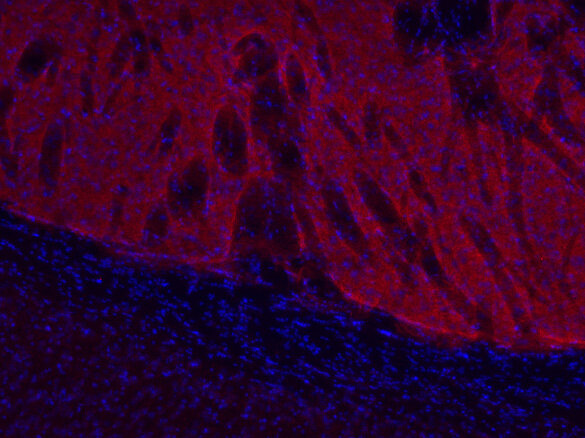

Dopamine receptor D1 antibody - 376 002

IHC: 1 : 500 gallery

IHC-P: 1 : 500 gallery

Specificity Specific for dopamine receptor D1. The antibody may have a weak crossreactivity to dopamine receptor D5.

Dopamine receptor D1 is widely distributed throughout the brain with the highest expression in the striatum. In the periphery, the D1 receptor has been detected in the adrenal cortex, kidney and heart. Recently, it was shown that dopamine receptor D1 is expressed in breast cancer, thereby identifying this receptor as a novel therapeutic target in this disease. D1 receptor overexpression is associated with advanced breast cancer and poor prognosis.